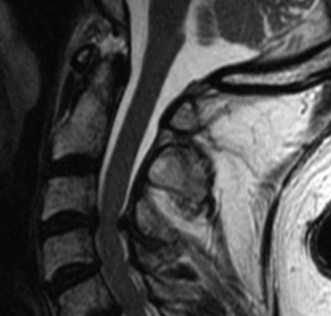

Magnetic Resonance Imaging and the Posterior Ligamentous Complex

To definitively assess the integrity of the soft tissue stabilizers and the neural elements, a Magnetic Resonance Imaging (MRI) scan without contrast was performed. Historically, textbooks propagated the "50-50-25 rule," suggesting that a burst fracture was inherently unstable if it exhibited >50% canal compromise, >50% loss of vertebral body height, or >25 degrees of kyphosis. Modern spine trauma surgery has largely debunked this rigid radiographic dogma. We now understand that these bony metrics alone do not dictate mechanical instability. The true arbiter of stability is the Posterior Ligamentous Complex (PLC).

The MRI, particularly the Short Tau Inversion Recovery (STIR) and T2-weighted sagittal sequences, provided the definitive diagnosis. The images demonstrated profound hyperintensity and discontinuity of the ligamentum flavum, the interspinous ligaments, and the supraspinous ligaments at the T12-L1 level. The facet joint capsules were also disrupted, indicated by fluid within the joints. This complete failure of the PLC means the posterior tension band is gone. Regardless of the bony parameters, this spine cannot resist physiological flexion loads. If treated non-operatively, this injury will inevitably lead to progressive kyphosis, delayed neurological deficit, and intractable pain.